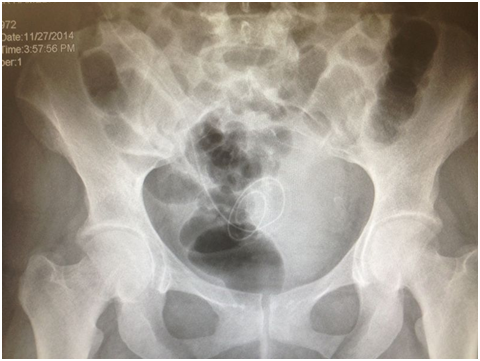

Figure 2E: Pelvic X-ray showing the Saudi catheter in position.

The procedure was carried out with patient in the supine position under general anesthesia using aseptic precautions. A verses needle was used to create pneumo-peritoneum at pressure of 10-12 mmHg. A 5-mm port was inserted in right hypochondreal region at midclavicular line, 2cm below the costal margin for laparoscopic camera (30 degree). Diagnostic laparoscopy was then performed to rule out adhesions or herniations (Figure 2-B & 2 C). The operating table was then placed in about 30 degree trend elenburg position. Under direct vision, the three-cuff Saudi catheter was passed caudally through the pull-apart sheath over a 90-cm stylet into the peritoneal cavity. Above the symphsis pubis the tip of the catheter was placed in the true pelvis (towards the urinary bladder), with the distal cuff in the rectus sheath before removing the stylet. The distal cuff of the catheter was secured with purse-string suture on the fascia anterior to the rectus muscle by using 2/0 absorbable vicryl stitches. The tip of catheter was in the pouch of Douglas and the rectovesical pouch in female and male respectively. The pull-apart sheath was removed, leaving the catheter in the peritoneal cavity (Figure 2-B, 2-C and 2 D). Following that, a subcutaneous tunnel was created for the catheter with selection of a midway point at the umblico-crestal line to be the output of the catheter. The end of the catheter attached to the stylet was advanced into the tunnel and pulled out from the above-mentioned point; the second cuff about 10 cm from the distal one and the proximal cuff 2 cm from the exit site. Figure 2-D and E illustrates the final position of the 3-cuff PD catheter. The function of the catheter was checked by flushing normal saline to rule out kinking or obstruction. The skin incisions of the camera port and entrance were sutured. Xylocaine with adrenaline diluted in normal saline was injected in the incision site and in the tunnel space.